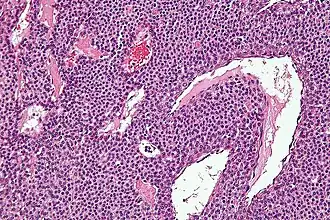

![]() Microfotografía de un tumor glómico | ||

El tumor glómico, también llamado glomus, es un tipo de tumor benigno que deriva de un tipo especial de células que reciben el nombre de células glómicas.[1]